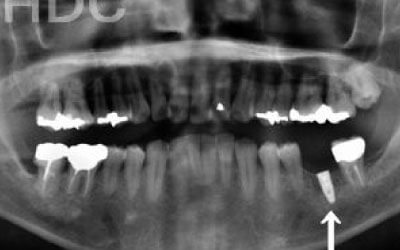

2 歯が傾いてくる、落ちてくる

歯は互いに支え合い、バランスを保っています。そのため、歯が抜けると支えがなくなり、抜けた部分の両隣の歯が傾いたり、上の歯が下に移動してきたりすることがあります。